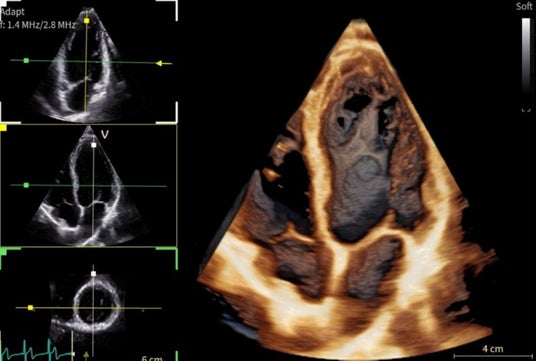

「Vivid Pioneer」は、これまで検査者が手作業で行っていた血流解析をAIが自動で行い、短時間で安定した測定プロセスを提供します。また、心臓の主要な部位(左心室と左心房)の動きや形を三次元で自動分析し、検査者間の標準化を支援します。そのほか、次世代の画像エンジン機能により、細部の見やすさ(空間分解能)や色の見やすさ(カラー感度)が向上し、より高精度な心臓の立体画像を描出します。

次世代の画像エンジンによる高精細な心臓画像